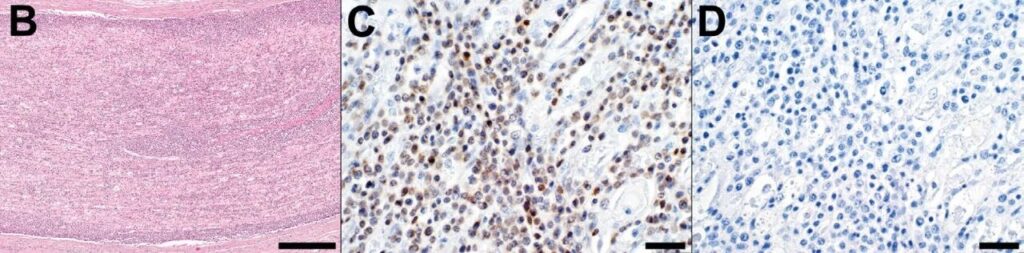

大脑仅见少量局灶性淋巴细胞性血管周围套环及轻度含铁血黄素沉着。此外可见多灶性血管周围水肿、寡灶性胶质细胞结节,以及多灶性神经元吞噬现象和卫星细胞增生。大脑及小脑的软脑膜、颅神经或脑实质中未见大淋巴细胞浸润。免疫组化检测可见浸润性大淋巴细胞表达CD3,未见PAX5免疫标记,由此确认为T细胞来源(下图)。

↑(B)病理学显示中间至大型圆形细胞(淋巴母细胞)组成的片状浸润并扩展至C6脊神经。(C)CD3(T细胞)阳性免疫组化染色。(D)PAX5(B细胞)阴性免疫组化染色。